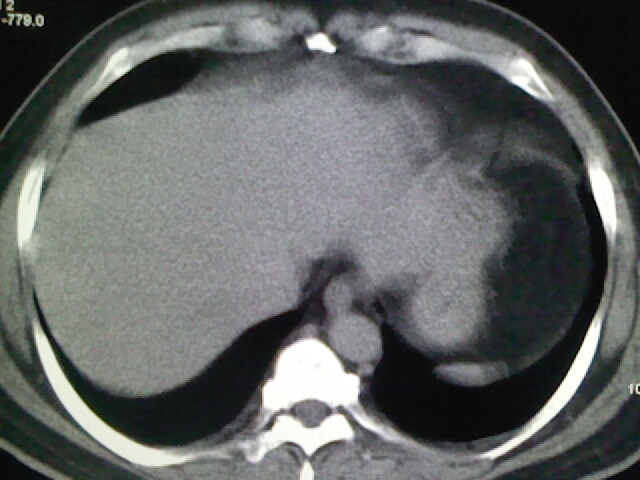

标题: CT17932:临床怀疑肺栓塞

男,34岁,自觉右侧胸痹,胸闷3天余

左上肺局限片状透光度增强区,肺纹理稀少,可考虑局限性肺气肿。

左上肺局限性肺透光度减低,肺纹理稀少;这虽然符合早期肺栓塞的改变,但与局限性肺气肿难以鉴别。

书上讲早期肺栓塞就是表现肺透光度减低,肺纹稀少。